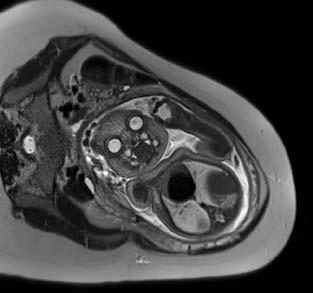

When an unborn baby has an abnormality, decisions about the delivery and neonatal care can often be planned in advance – with the help of an MRI.

MRI image acquisition can be tricky and quality reporting is an acquired skill. An expert in the field, Dr Lauren Raubenheimer honed her skills in London under world-renowned foetal and neonatal imaging specialist, Prof Mary Rutherford. Dr Raubenheimer joined SCP Radiology as a consulting radiologist.

“When a couple discovers their baby has an abnormality, the impact is enormous,” she explains. “I hope my findings give parents more answers as they navigate a difficult path.” With the help of an MRI, Dr Raubenheimer says that in many cases, the timing and route of delivery, as well as the neonatal care required, can be planned in advance.

Specialists after an abnormality has been detected on a screening ultrasound. An MRI can be done to confirm the abnormality, as well as to assess for abnormalities that are not readily visible through standard imaging techniques. This can significantly affect the prognosis. A foetal MRI can be performed either in the second or third trimester.

Dr Raubenheimer’s special interest is in developmental foetal brain abnormalities, but she also performs MRIs for body abnormalities, including congenital diaphragmatic hernia and spina bifida.

MRI can be superior to ultrasound in certain instances, such as assessing the folding of the brain and parts of the brain obscured by the skull, when amniotic fluid is low and when mothers have a high body mass index (BMI).

Foetal movement used to be an obstacle in getting good quality MR images. However, with today’s advanced magnets and faster imaging sequences, excellent image quality can be obtained. At SCP Radiology, foetal MRI scans are done exclusively by lead MRI radiographer Andrea Nagel.

Safety is, of course, of utmost importance. Dr Raubenheimer reassures us that present data shows no conclusively documented harmful effects of MRI imaging on the

developing foetus, providing it is at the safe and optimal level. She also adds that MRI does not use ionising radiation, and intravenous contrast is not administered in foetal MRI.

Foetal MRI is covered by medical aids, but pre-authorisation is required.

Dr Raubenheimer prefers that patients are referred from a Foetal Medicine Specialist after a detailed ultrasound. “Having access to ultrasound reports and knowing the exact gestation is crucial to an accurate MRI report,” she emphasises.